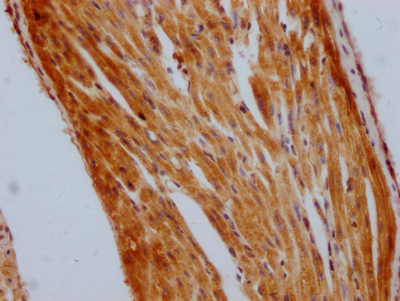

• IHC image of CSB-RA229700A0HU diluted at 1:100 and staining in paraffin-embedded human heart tissue performed on a Leica BondTM system. After dewaxing and hydration, antigen retrieval was mediated by high pressure in a citrate buffer (pH 6.0). Section was blocked with 10% normal goat serum 30min at RT. Then primary antibody (1% BSA) was incubated at 4℃ overnight. The primary is detected by a Goat anti-rabbit IgG polymer labeled by HRP and visualized using 0.05% DAB.